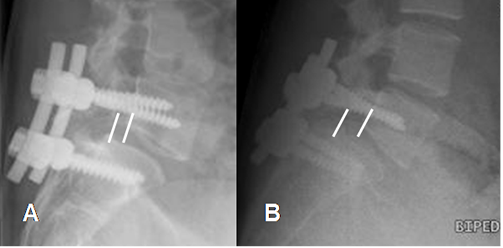

La inestabilidad dinámica PostQx, se define como el desplazamiento anterior o posterior mayor de 3 mm. Se debe medir el desplazamiento sagital entre las vértebras y la angulación entre las placas terminales en un espacio. (6). (Fig 133).

Fig 133. Inestabilidad postquirúrgica.

A: Rx lateral en reposo. Fijación posterior, con anterolistesis grado I de L4, sobre L5.

B: Rx lateral en flexión. Incremento de la anterolistesis, con la flexión.